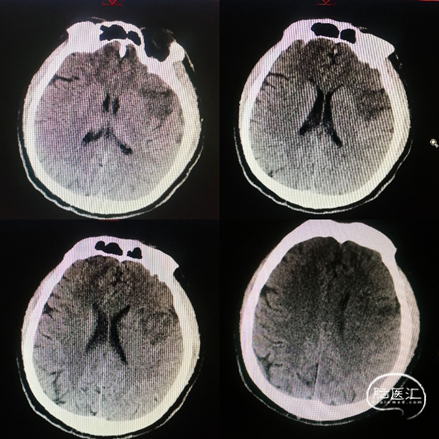

术前影像学

复查颅脑CT颞叶梗死表现:

核心梗死体积33.43ml,低灌注体积153.98ml,Mismatch120.55ml。